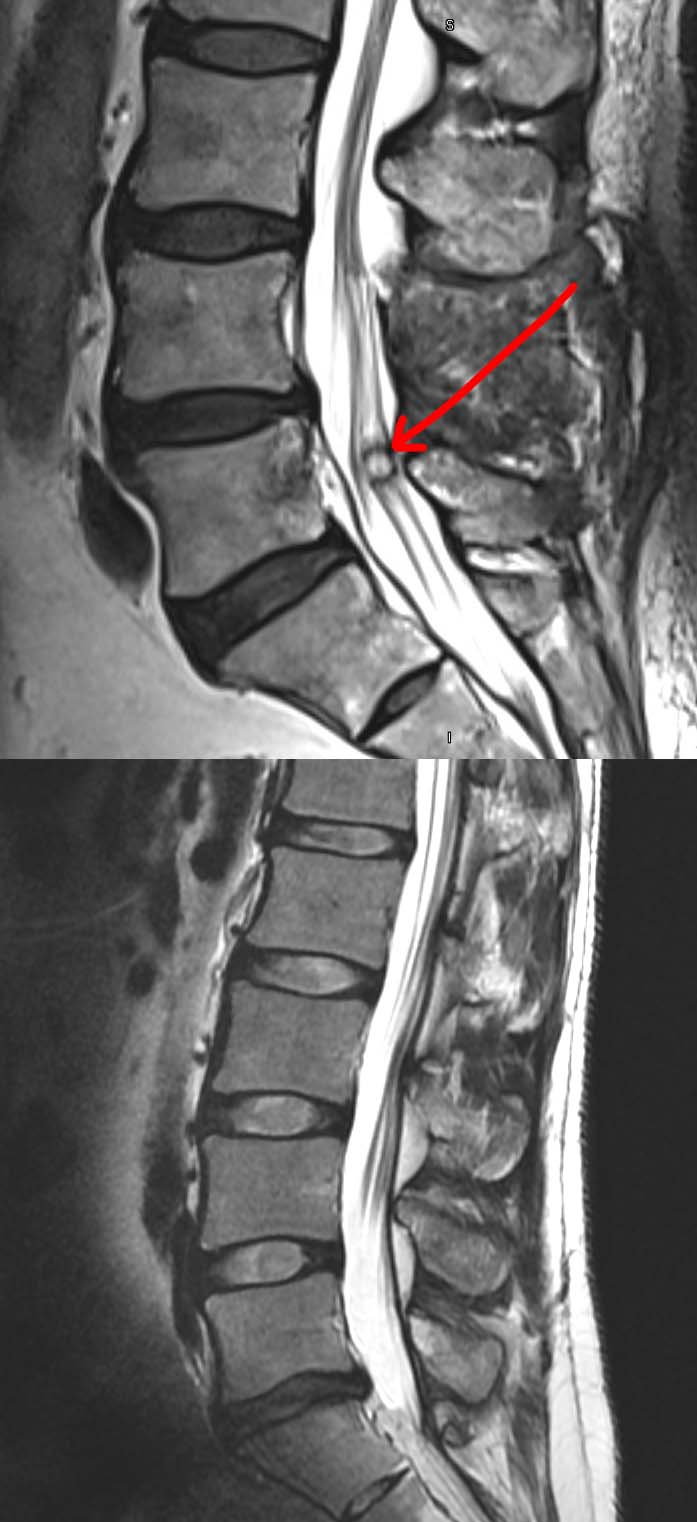

Synovial Cyst of the Spine — Back Muscle Cyst The goal of synovial cyst surgery is to remove the cyst to provide more room for the spinal column to eliminate pressure on the nerve roots. How can one distinguish between a soft lump and a hard lump on the A benign tumor made up of fat cells. It could also be a cyst or a benign bone growth like. Back Muscle Cyst.